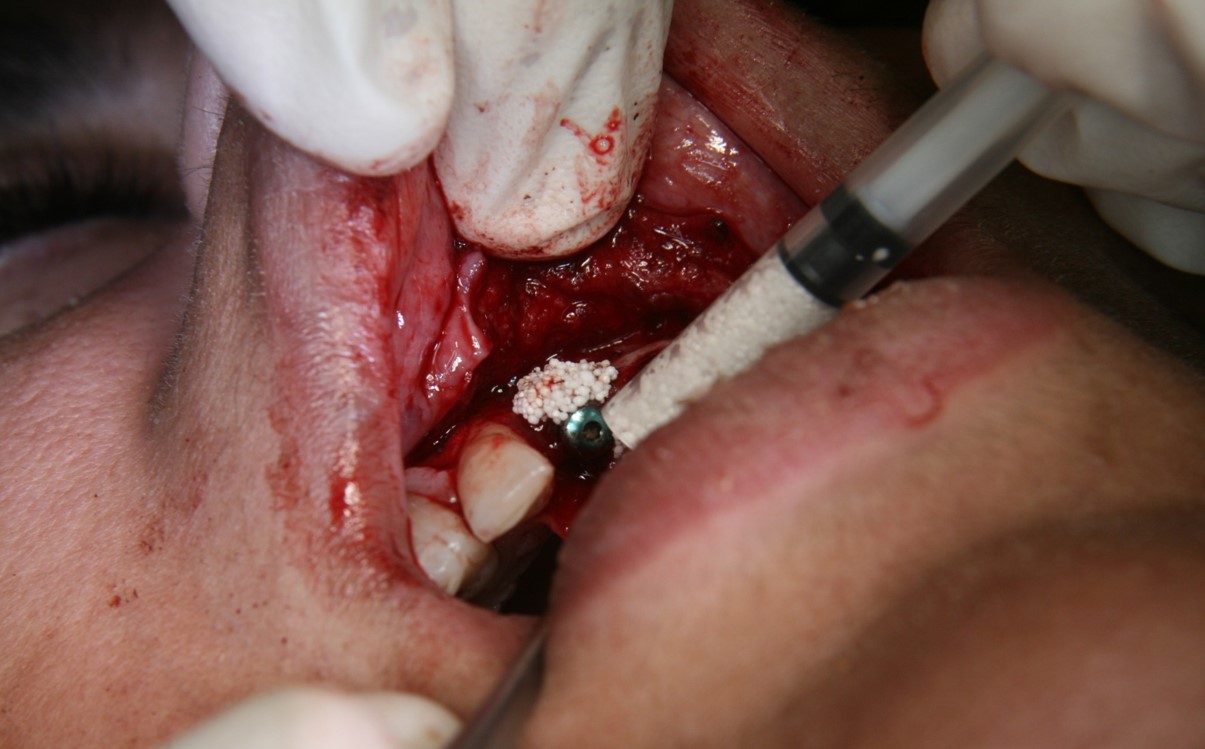

Fig 2. A PLGA alloplast bone grafting material was placed and molded to shape the area.

Figure 2

A new beta-tricalcium phosphate granule (PLGA) alloplast material (GUIDOR® easy-graft, Sunstar, www.guidor.com) was recently introduced that can be molded and shaped through the defect, where it can easily stay in place.11 After 2 minutes, the PLGA bone graft material, being a reverse thermoplastic (ie, becomes harder as it warms to body temperature), hardens into position without becoming compressed or deformed during patient movements, which helps to prevent bone/shape loss (Figure 8 through Figure 13).11 The benefit is the material acts as a 3D template to support the area being grafted as it is replaced by the patient’s own bone over time.